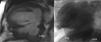

Case reportA 72-year-old male was referred to our institution due to a two-year history of progressive dyspnea. He had undergone inferior LVA resection and left internal mammary artery to left anterior descending artery (LAD) bypass eighteen years earlier. Physical examination revealed a grade II holosystolic apical murmur and the ECG showed previously unnoticed atrial fibrillation. Laboratory findings and chest radiography were unremarkable. Transthoracic echography revealed a dilated left atrium with mild mitral regurgitation. Left ventriculography showed a large bilobulated inferior aneurysm with dyskinetic wall motion (Figure 1A). Left ventricular systolic function was severely depressed, with an ejection fraction (EF) of 0.35 in the non-aneurysmal segments. Coronary angiography showed severe stenosis in the proximal LAD and occlusion of the right coronary artery. The internal mammary graft was patent. Magnetic resonance imaging (MRI) revealed a dilated left ventricle (LV) (163 ml/m2) with severely depressed global contractility (EF 0.20) and a large inferior aneurysm. An additional smaller basal pouch was also identified (Figure 1B).